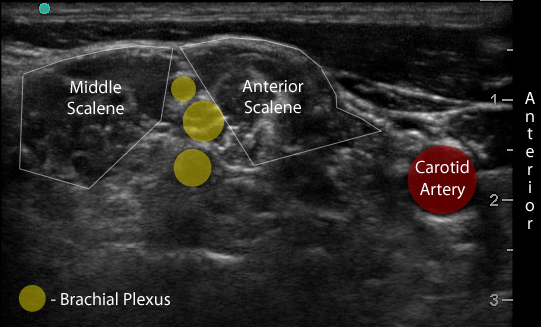

- Identify the middle scalene muscle posterior to the anterior scalene muscle.

- The interscalene space is between these 2 scalene muscles and contains the brachial plexus

- Visualize the brachial plexus here as a stack of circles with hypoechoic centers

- The plexus will look more echogenic, bundled and honeycombed in the caudal interscalene space

- Move the probe inferiorly to identify the anterior scalene muscle deep to the lateral border of the SCM. (Figure 2)

- Triangular muscle that is thicker caudally

- Lateral to the internal jugular vein

- If not apparent, slide the probe in a cranio-caudal direction along the lateral border of the SCM to find it